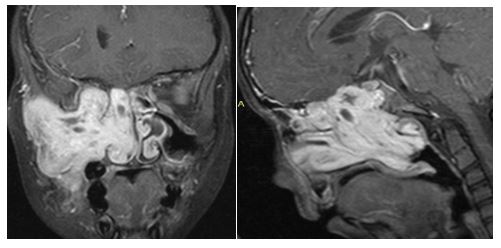

3. 10/2017. Masculino 17 años con obstrucción nasal de inicio gradual, epistaxis recurrente derecha, masa la cavidad nasal bilateral y abombamiento de paladar blando de 4 años de evolución. TC y RM con extensión a naso y orofaringe con extensión a seno maxilar, fosa pterigomaxilar, infratemporal derecha y extensión intracraneal mínima. Clasificación IIIA (Radkowski) IV (Chandler). Se realiza angiografía, embolización de ramas de carótida externa bilateral, y resección vía endoscópica, transpalatina y Degloving, resección de 95% de tumor con tumor residual en fosa infratemporal, posterior radioterapia, con reducción gradual de tumor en los últimos 8 meses.